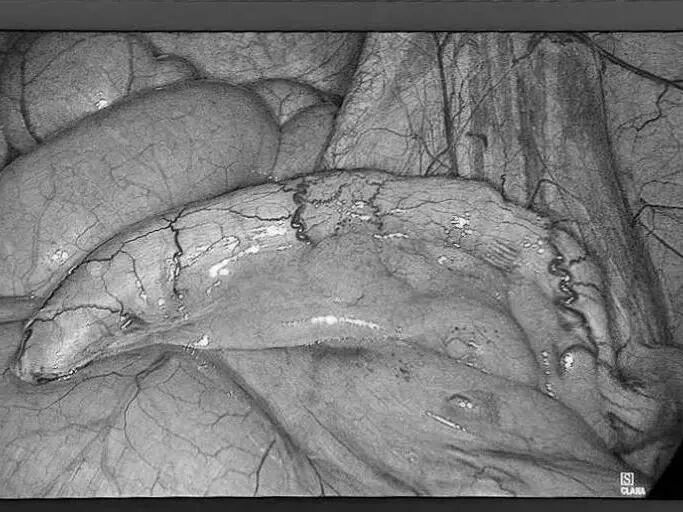

为更好地服务广大患者,贵州航天医院知名肛肠外科专家高大勇教授,每周二上午将固定坐诊贵州航天医院普外科。 坐诊信息 时 间:每周二上午(8:00-11:30) 地 点:贵州航天医院门诊部106诊室(普外科门诊) 挂号通道: 1.门诊大厅或诊室自助挂号缴费机。 2.门诊挂号缴费窗口。 3.贵州航天医院微信公众号预约挂号。 专家简介 高大勇 普外科(肛肠外科)学科带头人、名誉主任,主任医师、教授 临床擅长:对中西医结合诊治肛肠学科各种常见病、多发病及疑难杂症等具有丰富的临床经验。 原遵义市第一人民医院(遵义医科大学第三附属医院)、遵义市中医院肛肠科主任。中华中医药学会肛肠分会常委,全国中医肛肠学科名专家,中国健康促进与教育协会肛肠分会常委,中国康复医学会肛肠疾病康复专业委员会常委,中国民间中医医药研究开发协会肛肠分会副秘书长,中国医师协会中西医结合肛肠医师专业委员会常委,国家二级心理咨询师,贵州省第一批中医名医工作指导老师,遵义市名中医,遵义市肛肠学会会长,遵义市肛肠质控中心名誉主任,遵义市中西医结合学会名誉会长,遵义市健康科普专家,原贵州省中西医结合学会肛肠分会副主任委员、贵州省中医肛肠质控中心副主任、遵义市医学会医疗鉴定委员会专家、遵义市卫生系列高评委。发表论文30余篇,主编和参编医学著作5本,主持省级科研课题2项、市级科研课题2项、院级科研课题1项。 贵州航天医院 普外科简介 基本情况 贵州航天医院普外科成立于1968年,前身属于航天部O61基地3417医院外一科,1998年3417医院、3427医院合并后更名为普外科,下设胃肠外科、肛肠外科2个亚专业科室,拥有在全市较为先进的专科设备和技术,是中国疝病专科联盟单位,贵州医科大学附属医院胃肠外科专科联盟单位。开放床位40张,配备医护人员21人。 专科特色技术 普外科致力于胃肠及肛肠疾病的外科临床诊治及科研,以腹腔镜微创外科技术为本,形成以快速康复治疗胃肿瘤、结直肠肿瘤、小肠肿瘤、直肠脱垂、肥胖病、急腹症、各类疝、痔、瘘等专科特色,同时注重胃肠疾病尤其是结直肠恶性肿瘤的基础研究和临床转化研究,总体诊断和治疗水平在区域同级医院居于领先水平。 开展手术:腹腔镜下胃癌根治术,腹腔镜下袖状胃切除术,腹腔镜下胃肠道间质瘤切除术,腹腔镜下结、直肠癌根治术,胃癌、结直肠癌的精准治疗,腹腔镜下小儿疝气、成人疝修补术,腹腔镜下阑尾手术,内痔的硬化注射治疗及痔疮的微创治疗:ATH、PPH、TST,直肠脱垂的各种手术治疗,难治性伤口VSD技术,鼻胃肠管、肠梗阻导管置入术,肛肠术后间歇性导尿技术,并引进了中医适宜技术,也为各种化疗患者提供输液港安装,提高患者就医体验。 腹腔镜下腹股沟疝 无张力修补术 腹股沟疝里金斯坦(Lichtenstein)手术 PPH微创术治疗环状混合痔 黏连性或炎性肠梗阻-肠梗阻导管 腹腔镜袖状胃切除 腹腔镜阑尾切除术 腹腔镜阑尾肿瘤切除术 腹腔镜下结肠癌根治术 科室诊疗范围 胃肿瘤、结直肠肿瘤、小肠肿瘤、肥胖症、各类急腹症、腹部外伤、腹壁疝、便秘、直肠脱垂、痔疮、肛瘘、肛裂等胃肠、肛肠外科疾病。 END